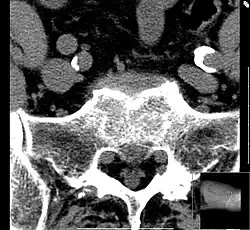

Iliosakralgelenksarthrose

Die Iliosakralgelenksarthrose ist eine Verschleißerkrankung (Arthrose) des Iliosakralgelenks (Kreuz-Darmbeingelenk).